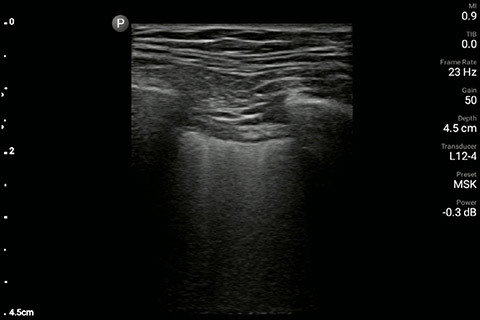

The patient had reduced LV systolic function without new or severe valvular pathology, a dilated, non-collapsing IVC, and diffuse B lines (left greater than right) on lung ultrasound imaging.

Lung image of the left chest

A 69 year-old male with a known history of hypertension, chronic non-oliguric kidney disease, insulin dependent diabetes, and chronic systolic heart failure with an ejection fraction (EF) of 25% secondary to ischemic cardiomyopathy was recovering in the CardioVascular ICU after four vessel coronary artery bypass grafting. His post-operative course had been complicated by acute respiratory failure, acute on chronic non-oliguric renal failure, delirium and pseudomonas pneumonia. The patient’s oxygenation had been improving on antibiotic therapy with aggressive diuresis and ionotropic support, although his BUN and creatinine remained quite elevated. Family had been reluctant to initiate dialysis given his clinical improvement and ability to make urine with diuretic support. The patient was extubated to high-flow oxygen by nasal cannula after successfully passing a spontaneous breathing trial, although, he had failed extubation one week prior secondary to acute dyspnea and hypoxia. Two days later, the patient began to have a fever, worsening shortness of breath with increased oxygen requirements, and inability to wean ionotropic and vasopressor support further. Because of concern for septic shock, the patient was given a total of 500ml of crystalloid overnight. Whole blood lactic acid levels returned at 1.6, serum creatinine increased from 5.8 to 6.11, and the patient’s fever and shortness of breath worsened. Repeat cultures were obtained and antibiotic therapy was broadened further while initiating non-invasive positive pressure ventilation for acute respiratory distress. In the interim, while awaiting laboratory results and chest X-ray imaging, POCUS with a three-point exam (F-TTE, IVC collapsibility, and lung ultrasound) was used for bedside evaluation of the etiology of the patient’s dyspnea. Within minutes, and with the additive information from the combined cardiac, subcostal IVC, and lung ultrasound imaging, the patient was diagnosed with acute on chronic congestive heart failure and flash pulmonary edema as the cause of his respiratory distress and hypoxia.